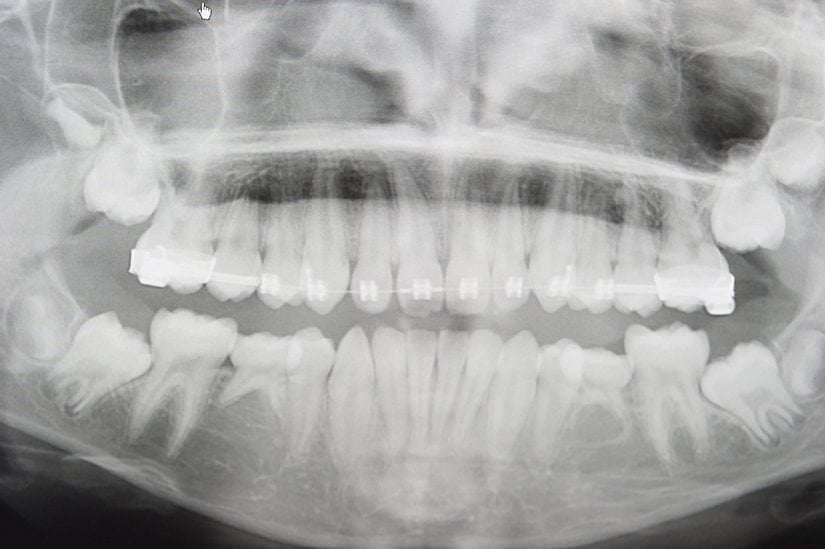

Yirmi yaş dişlerinin sıklıkla gömülü kalırlar, çıktıkları zaman doğru şekilde çıkmazlar ve diğer dişlere sürtünerek onların yapısını bozabilirler. Bu nedenle de ağrı ve enfeksiyona neden oldukları bilinmektedir. Bunun haricinde ise hiçbir işlevleri bulunmamaktadır. Dolayısıyla ağrıya neden oldukları zaman, diş hekimleri tarafından çekilerek hasta rahatlatılabilmektedir. 20 yaş dişleri çekilen kişilerin ağız fonksiyonlarında hiçbir azalma olmamaktadır. Aşağıda bu dişleri görmektesiniz:

Uzun yıllar insanlar bu dişlerin en başından neden var olduğunu anlayamamış ve bir çeşit "lanet" olarak görmüşlerdir; zira 20 yaş dişlerinin çıkmaya başlamasından çekilene kadar verdiği acıyı, bu dişleri sorunlu olarak çıkan kişiler gayet iyi bilirler. Ancak evrimsel biyolojinin gelişimiyle birlikte öncelikle insan evrimine ışık tutulmuş, daha sonra da bu tip körelmiş organların varlığı açıklanmıştır. 20 yaş dişleri de, insanda görülen 40'tan fazla körelmiş organ ve yapıdan sadece birisidir. Aşağıda, bu körelmiş yapıların ne şekilde hatalı oluşabileceklerine örnekler görülmektedir: